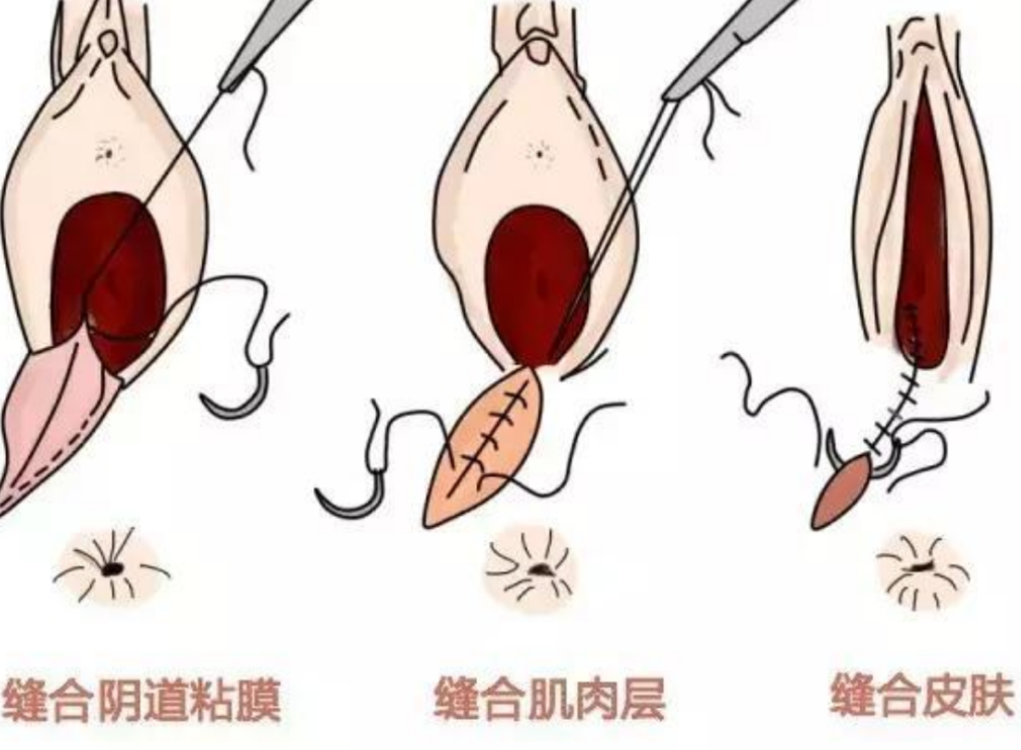

人工陰道漫畫的

治療中人工陰道漫畫

人工陰道漫畫

治療中人工陰道

治療中人工陰道漫畫

治療中人工陰道的

正在治療的人工陰道

治療中的人工陰道的

治療中的人工陰道

正常人工陰道的

正常人工陰道

幼兒人工陰道

正常的人工陰道的

正常的人工陰道

正常女性人工陰道

人工陰道治療中的

人工陰道作用

人工陰道治療

人工陰道治療前期

人工陰道治療前後